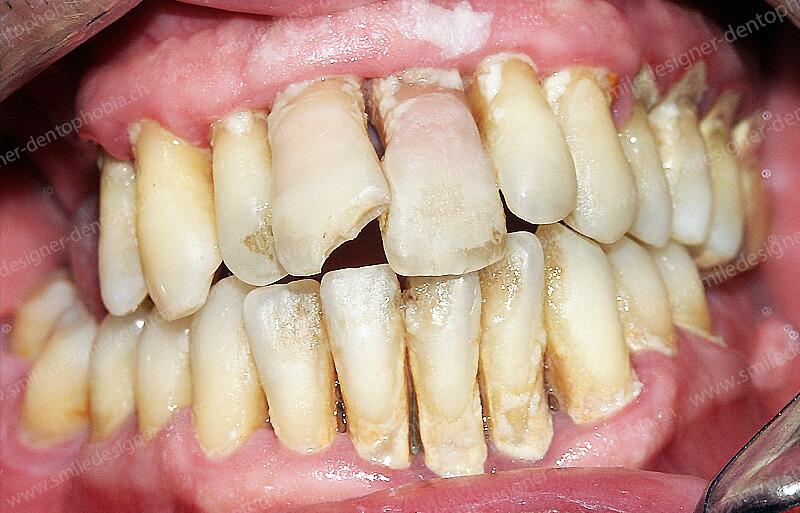

Cas clinique « GOLD STANDARD MCI » bi-maxillaire : Bridge implanto-porté sans extension postérieure (ALL ON 10). Version définitive des bridges avec un cosmétique en céramique.

Cas clinique « GOLD STANDARD MCI » bi-maxillaire : Bridge implanto-porté sans extension (ALL ON 8) au maxillaire et à la mandibule. Version définitive des bridges avec un cosmétique en céramique.

Cas clinique « GOLD STANDARD MCI » maxillaire : Bridge implanto-porté sans extension (ALL ON 8). Version définitive des bridges avec un cosmétique en céramique.

Cas clinique « GOLD STANDARD MCI » maxillaire : Bridge implanto-porté sans extension (ALL ON 10). Version définitive des bridges avec un cosmétique en céramique.

Cas clinique « GOLD STANDARD MCI » bi-maxillaire : Bridge implanto-porté sans extension (ALL ON 10). Version définitive des bridges avec un cosmétique en céramique.

Cas clinique « GOLD STANDARD MCI » bi-maxillaire : Bridge implanto-porté sans extension (ALL ON 8). Version définitive des bridges avec un cosmétique en céramique.